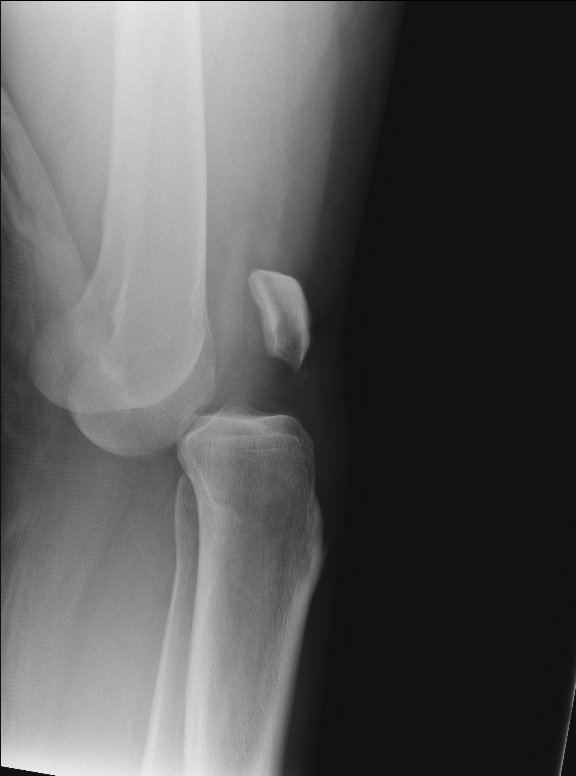

Osgood-Schlatter disease

Osgood-Schlatter disease @lifeinthefastlane.com